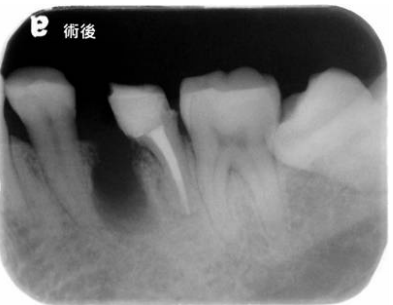

13. 下方是左下第一大臼齒術前與術後的X光片,請問所接受的治療術式為何?

(A)根尖切除術(apicoectomy) (B)牙冠切斷術(crown amputation) (C)牙根切斷術(root amputation) (D)半切斷術(hemisection)